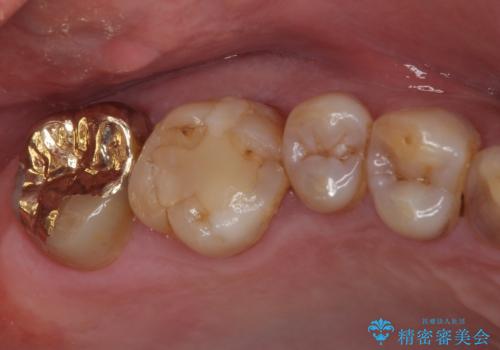

- 銀歯が外れてしまったとのことで来院された患者様です。

上顎奥の粘膜に近い部分で、外れた銀歯の下には大きく虫歯が広がっていました。

虫歯をしっかりと取り除き、ゴールドインレーにて修復することとしました。

ゴールドインレーは銀歯のインレーやセラミックインレーと比べ、「技工操作の精度が高く、適合が著しく良い」というメリットがあります。特に上の奥歯は歯科医師の操作が行いにくいため、「適合の良さ」は再治療のリスクを防ぐ上でとても重要な要素となります。

上の奥歯は金属色が見えることもないため、審美的な問題は全くありません。

咬み心地はとても良好で、全く違和感がなく、患者様には大変満足していただきました。